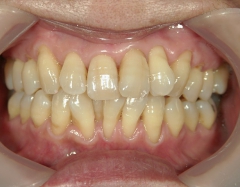

矯正歯科 治療後矯正歯科 プチワイヤー矯正 治療後矯正歯科(プチワイヤー矯正)治療後

矯正歯科 治療後

no.12_5333_治療後_左.jpgno.12_5333_治療後_正面.jpgno.12_5333_治療後_右.jpg